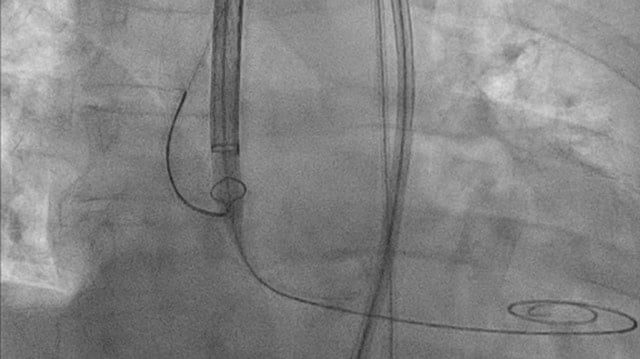

How to snare a TAVI when crossing is too complex

Crossing the aortic valve can pose significant challenges, particularly in cases involving a horizontal aorta, bulky asymmetric calcifications, or prior prosthesis implantation in valve-in-valve procedures. While some TAVI devices feature deflectable delivery systems to enhance coaxiality, current self-expanding valves lack this capability. When standard techniques like...